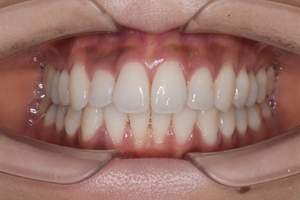

プロフェショナルクリーニング(PMTC)

治療前

治療後

| 年齢 | 26歳・女性 |

|---|---|

| 主訴 | 主訴:着色除去 治療部位:全顎 |

| 治療内容 | PMTC(自費診療) |

| 治療期間 | 30分 |

| 費用 | 5,500円 (2023年5月現在) |

| リスク・副作用 | ・生活習慣(喫煙・コーヒーなど)により再度着色することがあります。 ・PMTCは歯を白くするものではなく着色・バイオフィルムの除去を目的としています。 ・保険適用外の施術です。 |

| 治療方針 | プロフェショナルクリーニング(PMTC)後ホワイトニングを行う予定です。 |

| 特記事項 | 右下3番、2番の間に着色が目立ち、歯ブラシの動かし方の確認を行うとストロークが大きく、着色部位に歯ブラシが当たっていませんでした。歯ブラシが歯面に当たる角度を確認し、細かく振動を送るように動かすよう指導しました。一緒にステイン除去効果のある歯磨剤のおすすめを行いました。 |

| 担当者所見 | 右下3番、2番の間の着色が気になると来院されPMTCを行いました。喫煙の習慣はなく日常的にコーヒーを飲んでいるとのことでした。クリーニング後は歯がツルツルになったと喜んでくださいました。 |